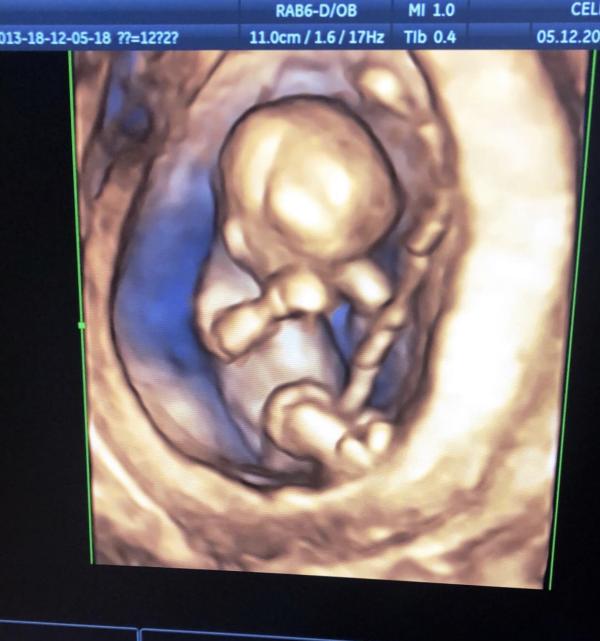

Пошла я на первый скрининг с мужем,всю дорогу спорили я говорю девочка,а он мальчик😂

Всем на свете снился сон что у меня родилась девочка и я чувствовала что ну уж точно будет девочка,я умирала хотела девочку😭😭

И вот узистка говорит у вас мальчик 👶🏻 муж чуть ли лезгинку не танцует там🤣а я лежу глаза 😳вот такие,слезы текли налево слезы текли направо😂😂и спрашиваю точно мальчик? Может все таки девочка?🤔

Теперь муж звонит и говорит поздравляем у вас мальчик 😂 а я говорю ой извините молодой человек мы...